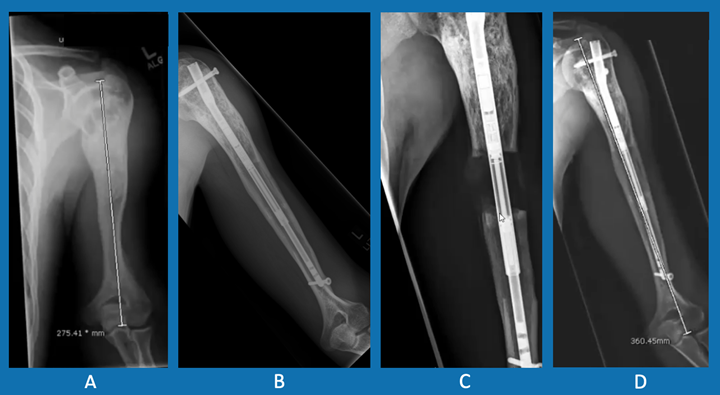

There are two types of limb-lengthening devices. One type is worn on the outside of the arm or leg. The other is an internal device that is more precise and reduces the risk of complications and infection.

External fixators are worn on the outside of the limb and are attached to the bone by pins. The patient or family adjusts the device daily to increase the distance between the two ends of bone. Once the correct length is reached, the device remains on the leg or arm while the new bone hardens and becomes strong. The device is then surgically removed.

The internal fixator (PRECICE Nail) is a nail that is surgically inserted inside the bone after the osteotomy. Using an external magnet that causes the nail to expand, the patient or family slowly lengthens the bone a tiny amount each day until the desired length is reached. Like the external fixator, the internal fixator is removed once the limb has been lengthened and new bone has formed.